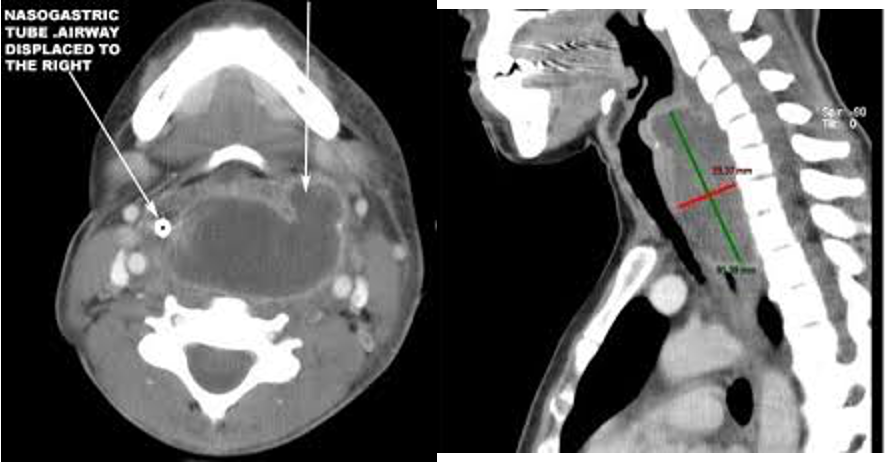

- respiratry distress

- INTUBATION

- Tracheotomy